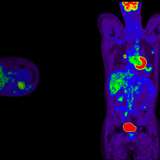

PET/CT scan for nuclear medicine

Cancer,

Science & Research

UCLA Health launches Department of Nuclear Medicine and Theranostics

The new department will drive the next generation of discovery and patient-centered care by integrating advanced imaging and therapy, accelerating scientific discovery and advancing precision health at UCLA Health.

figure of PSMA PET scans

New therapy delays progression of recurrent prostate cancer

Patients with recurring prostate cancer who were treated with a new PSMA-targeted radioligand therapy before stereotactic body radiotherapy went more than twice as long without their disease worsening compared with those who received SBRT alone.